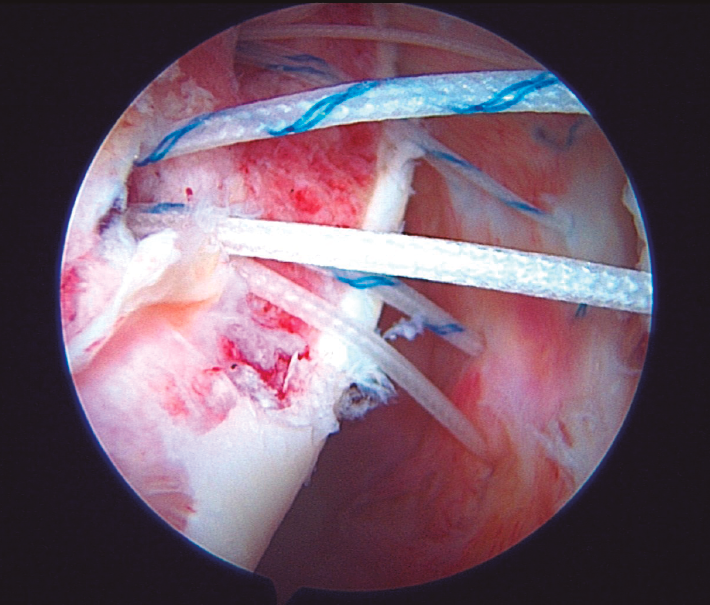

La técnica artroscópica de remplissage constituye actualmente una opción muy razonable para, asociada a la reparación de la lesión de Bankart, acometer el tratamiento de la inestabilidad anterior en pacientes con defectos óseos combinados en el lado glenoideo (≤ 20%) y en el humeral (independientemente de su tamaño). La técnica fue desarrollada por Wolf en 2008 para tratar defectos humerales de tipo Hill-Sachs grandes y consiste en una plicatura del infraespinoso sobre el defecto humeral. Tras escarificar la superficie ósea del defecto, se colocan dos implantes de dos suturas próximos al borde cartilaginoso del defecto. Se hace traspasar a cada sutura a través del tejido capsular y del infraespinoso con ayuda de alguno de los diferentes dispositivos de paso de los que disponemos. Las suturas quedan así pasadas por puntos independientes en la misma línea medio-lateral (en la imagen, en un hombro derecho con visión superior e instrumentación desde el portal a las 8:00) y son anudadas de forma ciega sobre el infraespinoso.

Tras escarificar la superficie ósea del defecto, se colocan dos implantes de dos suturas próximos al borde cartilaginoso del defecto. Se hace traspasar a cada sutura a través del tejido capsular y del infraespinoso con ayuda de alguno de los diferentes dispositivos de paso de los que disponemos. Las suturas quedan así pasadas por puntos independientes en la misma línea medio-lateral (en la imagen, en un hombro derecho con visión superior e instrumentación desde el portal a las 8:00) y son anudadas de forma ciega sobre el infraespinoso.